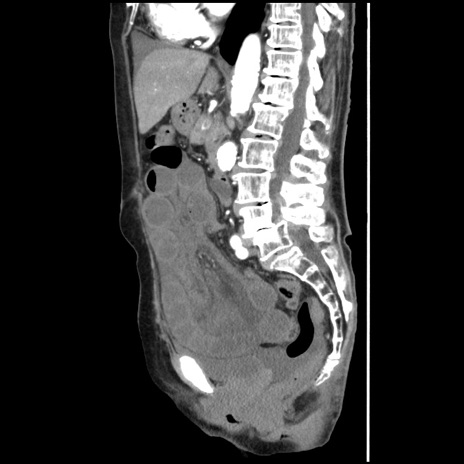

症例1(矢状断像)

【症例】80歳代女性

【主訴】腹痛

【現病歴】8時間前から腹痛あり来院。

【既往歴】糖尿病、脂質異常症、子宮体癌にて子宮全摘術

【身体所見】意識清明・会話良好だが腹痛で苦悶様、全腹部にわたって反跳痛と圧痛あり

【データ】WBC 13600、CRP 0.14、LDH 224、CK 90